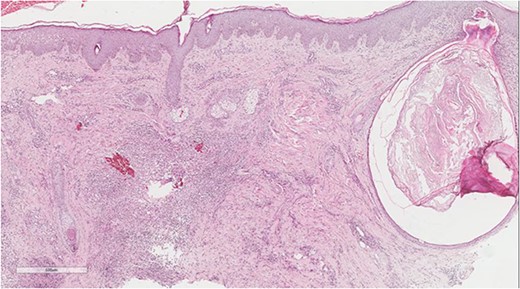

A 5 mm skin punch biopsy was also taken from the neck. Histopathology showed cystically dilated hair follicle with surrounding fibrosis and heavy inflammatory infiltrate and granulation tissue (Fig. 1), the inflammatory infiltrate is composed of lymphocytes, plasma cells, neutrophils and histiocytes (Fig. 2). The overall morphologic picture was suggestive of follicular occlusion syndrome (Fig. 3). A diagnosis of HS was made, and the patient was started on rifampin 600 mg OD and clindamycin 300 mg BID. A lipid panel was ordered as well and showed a triglyceride level of 1.99 mmol/L (0.7–1.7 mmol/L).

Dilated hair follicle with perifollicular inflammation and adjacent foreign body giant cell reaction secondary to ruptured dilated hair follicle in a background of dermal fibrosis.

Perivascular lymphoplasmacytic infiltrate that is a common finding in HS.